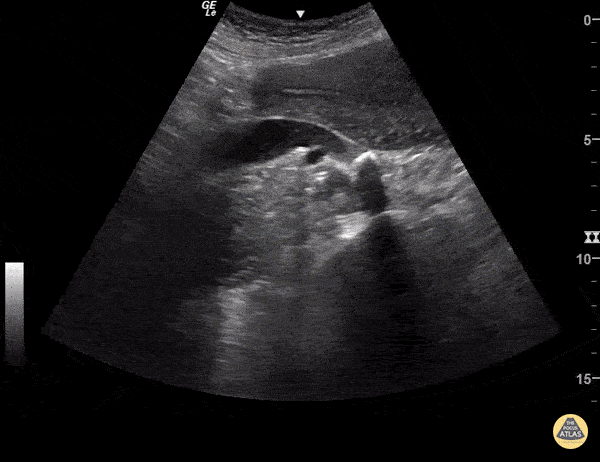

Renal/GU - Hydroureter with Stone

A dilated ureter is visualized posterior to the uterus in this transabdominal POCUS, indicating obstruction. The stone can be directly visualized as a hyperechoic structure in the ureter with shadowing. Sukh Singh, MD